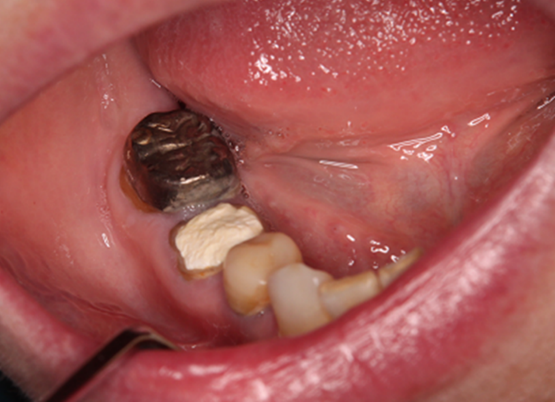

In an intraoral examination, temporary sealing with cement was observed on the right mandibular first molar (Figure 1A). Although intraoral examination showed no obvious gingival swelling around the roots of the right mandibular molar region, panoramic radiography showed a cystic lesion around the root apices of the right mandibular first molar (Figure 2A-C). Therefore, we selected tooth extraction and cystectomy as treatment. Although the patient’s preoperative platelet count was 36×103/μL, which was below the normal range, we performed tooth extraction and cystectomy under intravenous sedation without platelet transfusion based on the hematologist’s opinion that the patient was at low risk of hemorrhagic diathesis. No abnormal bleeding was observed in the socket, and the operative site was packed with Surgicel® (Ethicon Inc., New Brunswick, NJ, USA) and suture; a splint was then placed for hemostasis.

Figure 1. Intraoral photographs taken at the first visit to our hospital. The first molar was temporarily sealed with cement.